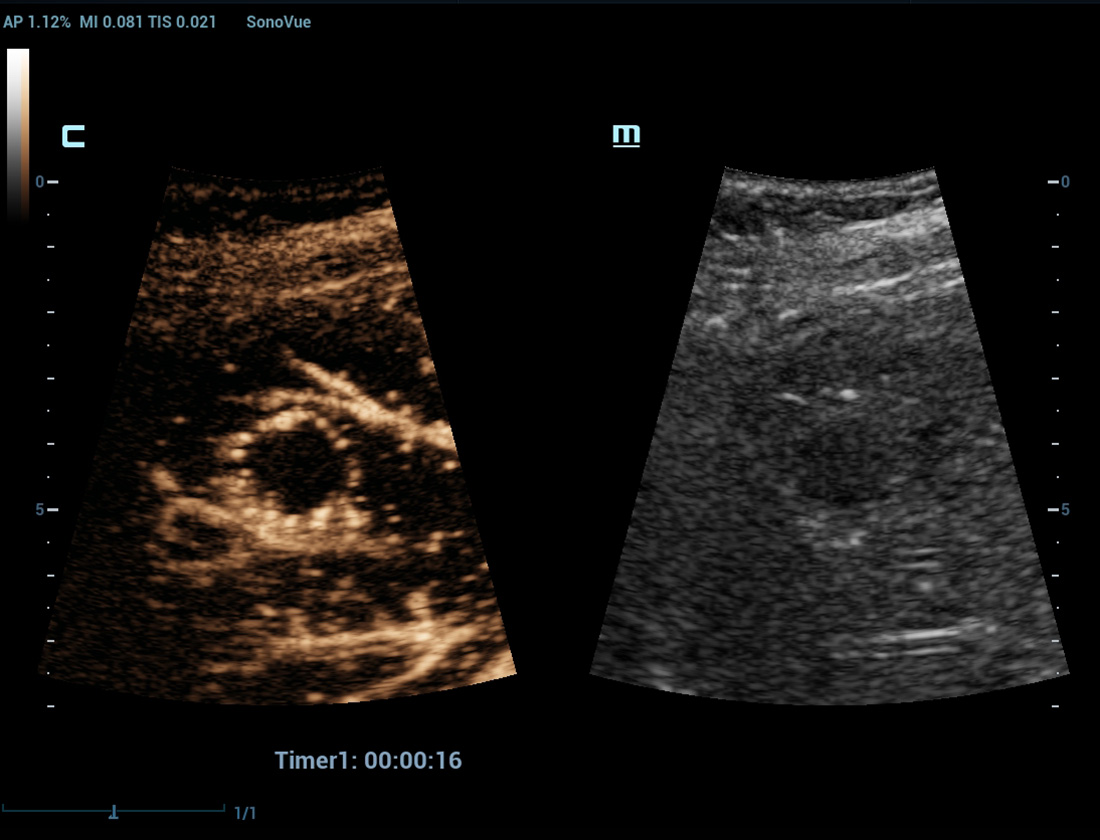

CEUS avanzata

CEUS UWN+(Ultra-Wideband Non-linear)

CEUS tumore maligno al seno

Utilizzando sia i segnali fondamentali di seconda armonica che quelli non lineari, UWN+ consente un'elevata sensibilitĂ ai segnali delle microbolle e una perfusione di contrasto piĂč lunga con un MI piĂč basso, per contribuire alla valutazione dei tumori.

Nuova analisi quantitativa CEUS

Nuova QA CEUS tumore maligno al seno

La curva tempo-intensitĂ offre un'analisi quantitativa dell'imaging CEUS. La Nuova QA CEUS fornisce strumenti di analisi quantitativa all'avanguardia per la valutazione dei tumori e la ricerca clinica.